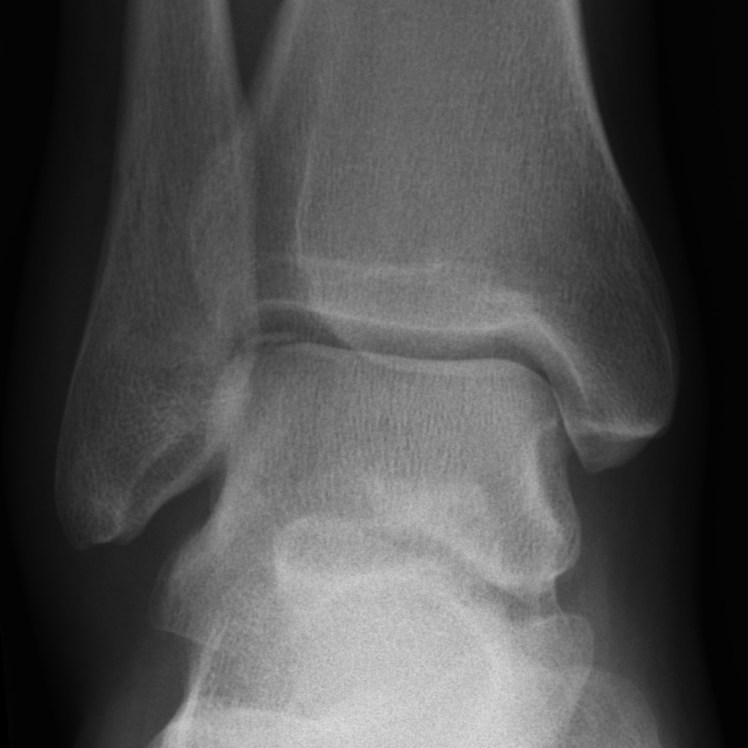

What’s the diagnosis? Gepost op 30 augustus 2017 door netwerkvsseh 40 yo male unable to weight-bear following an ankle inversion injury. What’s your diagnosis? @raediopaedia.org Dit delen: Delen op X (Opent in een nieuw venster) X Share op Facebook (Opent in een nieuw venster) Facebook Delen op LinkedIn (Opent in een nieuw venster) LinkedIn E-mail een link naar een vriend (Opent in een nieuw venster) E-mail Afdrukken (Opent in een nieuw venster) Print Vind-ik-leuk Aan het laden... Gerelateerd